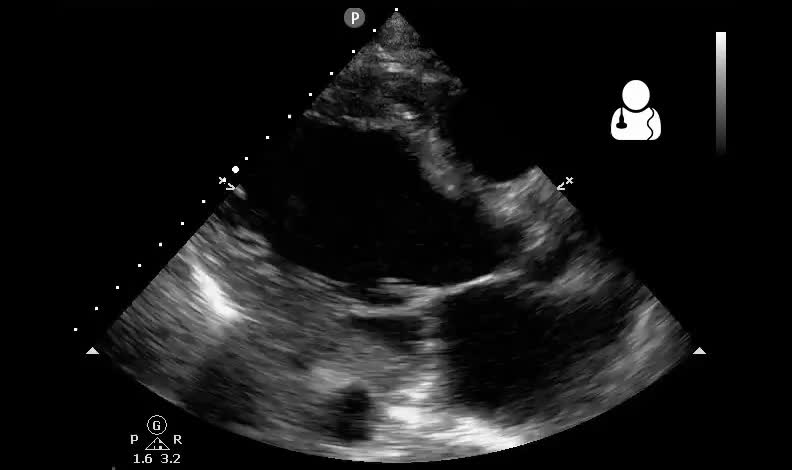

Una diagnosi formale richiede la presenza di sintomi tipici (dispnea, astenia, edemi) accompagnati da segni clinici (tachicardia, tachipnea, turgore giugulare) e la conferma di una sottostante causa cardiaca, identificata tramite imaging (ecocardiografia) o livelli elevati di peptidi natriuretici.2

L’ecocardiografia colordoppler è lo strumento principe per definire la frazione di eiezione e le alterazioni valvolari e cardiache.